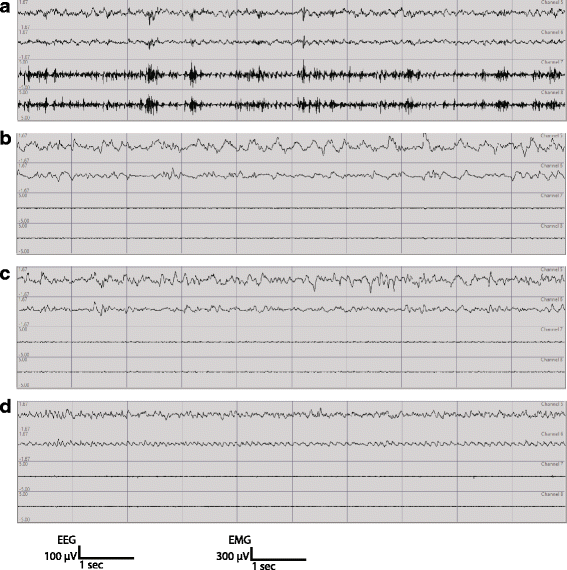

摘要:人类研究表明,睡眠障碍是自闭症谱系障碍(ASD)的并发合并症,但其病因在很大程度上仍不确定。ASD的一个突出理论表明,突触兴奋/抑制的不平衡可能会导致ASD的各个方面,包括睡眠障碍。与ASD患者神经连接蛋白3 R451C的鉴定,在小鼠模型中,它对突触传递和社会行为的影响已被广泛研究。然而,这种突变对ASD患者睡眠障碍的贡献尚不清楚。在这项研究中,神经连接蛋白3 R451C敲除小鼠显示睡眠/觉醒状态的持续时间和分布正常。但对清醒和睡眠的脑电图(EEG)功率谱有显著改变。关键词:神经连接蛋白3 R451C小鼠模型 自闭症 EEG NREM REM 睡眠不足简介:自闭症谱系障碍(ASD)是一类普遍的神经发育障碍,110个儿童中影响1个。ASD的诊断基于社交互动障碍、沟通障碍、行为刻板和限制。此外,睡眠障碍被认为是这一人群中最常见的症状之一。据报道,自闭症儿童40至80%有睡眠障碍。研究表明,睡眠质量差会加重ASD的核心症状和行为措施。强调了解和治疗ASD睡眠异常的重要性。例如,睡眠剥夺后社会和通讯赤字的严重程度加剧。此外,睡眠障碍也与增加的攻击性、易怒、多动和情感问题有关,可能会进一步损害ASD患者的日间功能。尽管睡眠障碍的自闭症人群的普遍性,但它的神经化学基础仍不清楚。ASD通常诊断年龄在2岁至4岁之间,发育期具有广泛的活动依赖性神经元重塑,其症状在成年期持续存在。SD病因的一个突出的神经化学概念是兴奋/抑制(E I)不平衡理论提示神经网络的兴奋性改变可能是ASD的特征。上调AMPA受体(快速兴奋性突触传递的主要介质),在ASD尸检患者脑样本中发现。同时发现γ-氨基丁酸(GABA)受体抑制剂的下调。此外,皮质和皮质下的兴奋性异常也被认为是ASD睡眠损害的一个重要因素。神经连接蛋白,突触后细胞粘附蛋白家族,通过GABA和谷氨酸能突触强度调节对神经元E/I平衡至关重要。在这项研究中,我们采用脑电图(EEG)-肌电图(EMG)记录评价神经连接蛋白3 R451C基因敲入小鼠睡眠质量(KI)。我们证明了这些小鼠在清醒和睡眠中的脑电图谱改变。方法:动物、饲养条件和基因分型:成年神经连接蛋白3 R451C基因敲入小鼠及野生型小鼠,饲养在12/12明暗环境中,自由采食和饮水。立体定位手术:成年雄性野生型小鼠,体重33.4±0.7g,周龄:19.1±1.0周,n=7.。神经连接蛋白3 R451C基因敲入小鼠,体重30.6±0.6g,周龄:19.3±11周,n=7.。用于外科手术。三个皮层电极脑电图记录和两绝缘不锈钢丝肌电图记录在植入前被焊接到多通道连接器上。动物在手术前用氯胺酮(100 - 150mg/kg,腹腔注射,IP)和甲苯噻嗪(7-10 mg/kg)作为术前麻醉。三个电极通过颅骨中的孔插入并放置在硬脑膜上,在小脑,左侧额叶和右顶叶。另外,将2条不锈钢丝缝合在颈部肌肉中。牙科丙烯酸将多通道连接器固定到头盖骨上。手术后,酮洛芬(5 mg/kg,皮下注射)给药用于术后止痛。数据采集:所有的小鼠都在笼子里至少饲养8天。EEG-EMG记录48h之前,在记录间适应3天。14只神经连接蛋白3 R451C基因敲入小鼠及其野生型(WT)小鼠用于EEG-EMG记录。记录过程中的光暗周期与饲养房间条件保持一致。对脑电和肌电信号进行记录、放大和滤波。睡眠-觉醒状态测定:独立的调查者对48小时的记录进行睡眠唤醒状态视觉评分。检查脑电图和肌电信号并分为清醒,NREM睡眠和REM睡眠。脑电频谱分析:利用matlab对两个脑电通道进行相减得到单个脑电信号。结果:神经连接蛋白3 R451C突变的小鼠在一天中表现出正常睡眠清醒的时间分布。ASD患者睡眠时间缩短,夜间觉醒时间延长,睡眠节奏也发生改变。分析了小鼠在明暗阶段,警戒状态和分布情况。神经连接蛋白3 R451C突变的小鼠同野生型小鼠在清醒、NREM睡眠和REM睡眠方面差异不显著。为确定神经连接蛋白3 R451C突变小鼠对警觉状态分布的影响,分析了一天的状态,同野生型相比,没有发现显著差异。ASD患者经常报道有更多的睡眠或更频繁的觉醒。神经连接蛋白3 R451C突变不明显影响整体睡眠/唤醒时间或有助于睡眠。